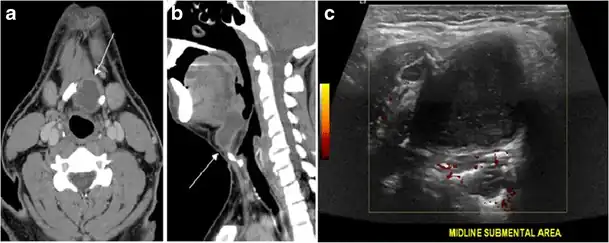

Fig. 13. A 27-year-old female patient known to have goiter. a, b Axial and sagittal enhanced CT scan images of the neck demonstrate a heterogeneously enhancing, enlarged thyroid gland with scattered calcifications (white arrow), cystic changes, and substantial retro-sternal extension (black asterisks). No lymphadenopathy or substantial airway narrowing.[1] -

Fig. 17. Ectopic thyroid on the left parotid gland with a palpable left parotid mass in a 69-year-old male patient. a, b Axial and coronal enhanced neck CT scan demonstrates well-defined homogeneous enhancing mass (white arrows) within the left parotid gland with preserved surrounding fat planes. It also shows a normal thyroid in normal position in the lower neck. c Image taken 20 minutes after 5 mCi injected Tc99m-Pertechnetate shows normal thyroid uptake of tracer and physiological uptake in the salivary glands (short black arrow). There is a distinct focus of abnormal tracer accumulation in the left parotid/submandibular region. Patient was given lemon juice with evident normal washout from the salivary glands and relative retention by this abnormal focus (long black arrow).[1] -

Fig. 20. Recurrent/residual thyroglossal duct cyst in a 39-year-old male patient. The first resection of thyroglossal duct cyst showed histopathology evidence of Hurthle cell type thyroid cancer. However, the second resection showed signs of chronic inflammation, with no malignant cells. a, b Enhanced axial and sagittal neck CT scans demonstrate a unilocular cystic lesion arising from the tongue base and extending through the partially resected hyoid bone. This cystic lesion has a peripheral enhancing wall, which becomes more thick over its inferior aspect associated with surrounding fat stranding at the surgical site (white arrow). There are no internal septations, nodules or masses, or calcifications. c Transverse view of power Doppler ultrasound at the submental area demonstrates cystic lesion and internal debris with no detected internal vascularity.[1] -